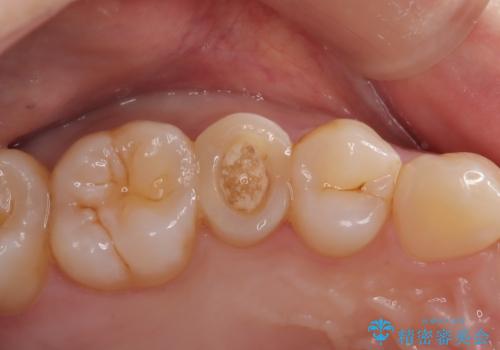

銀歯の下に虫歯 〈オールセラミッククラウン〉

担当医 瀧村怜未